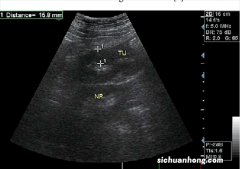

- 彩超为啥出来的是黑白图像?